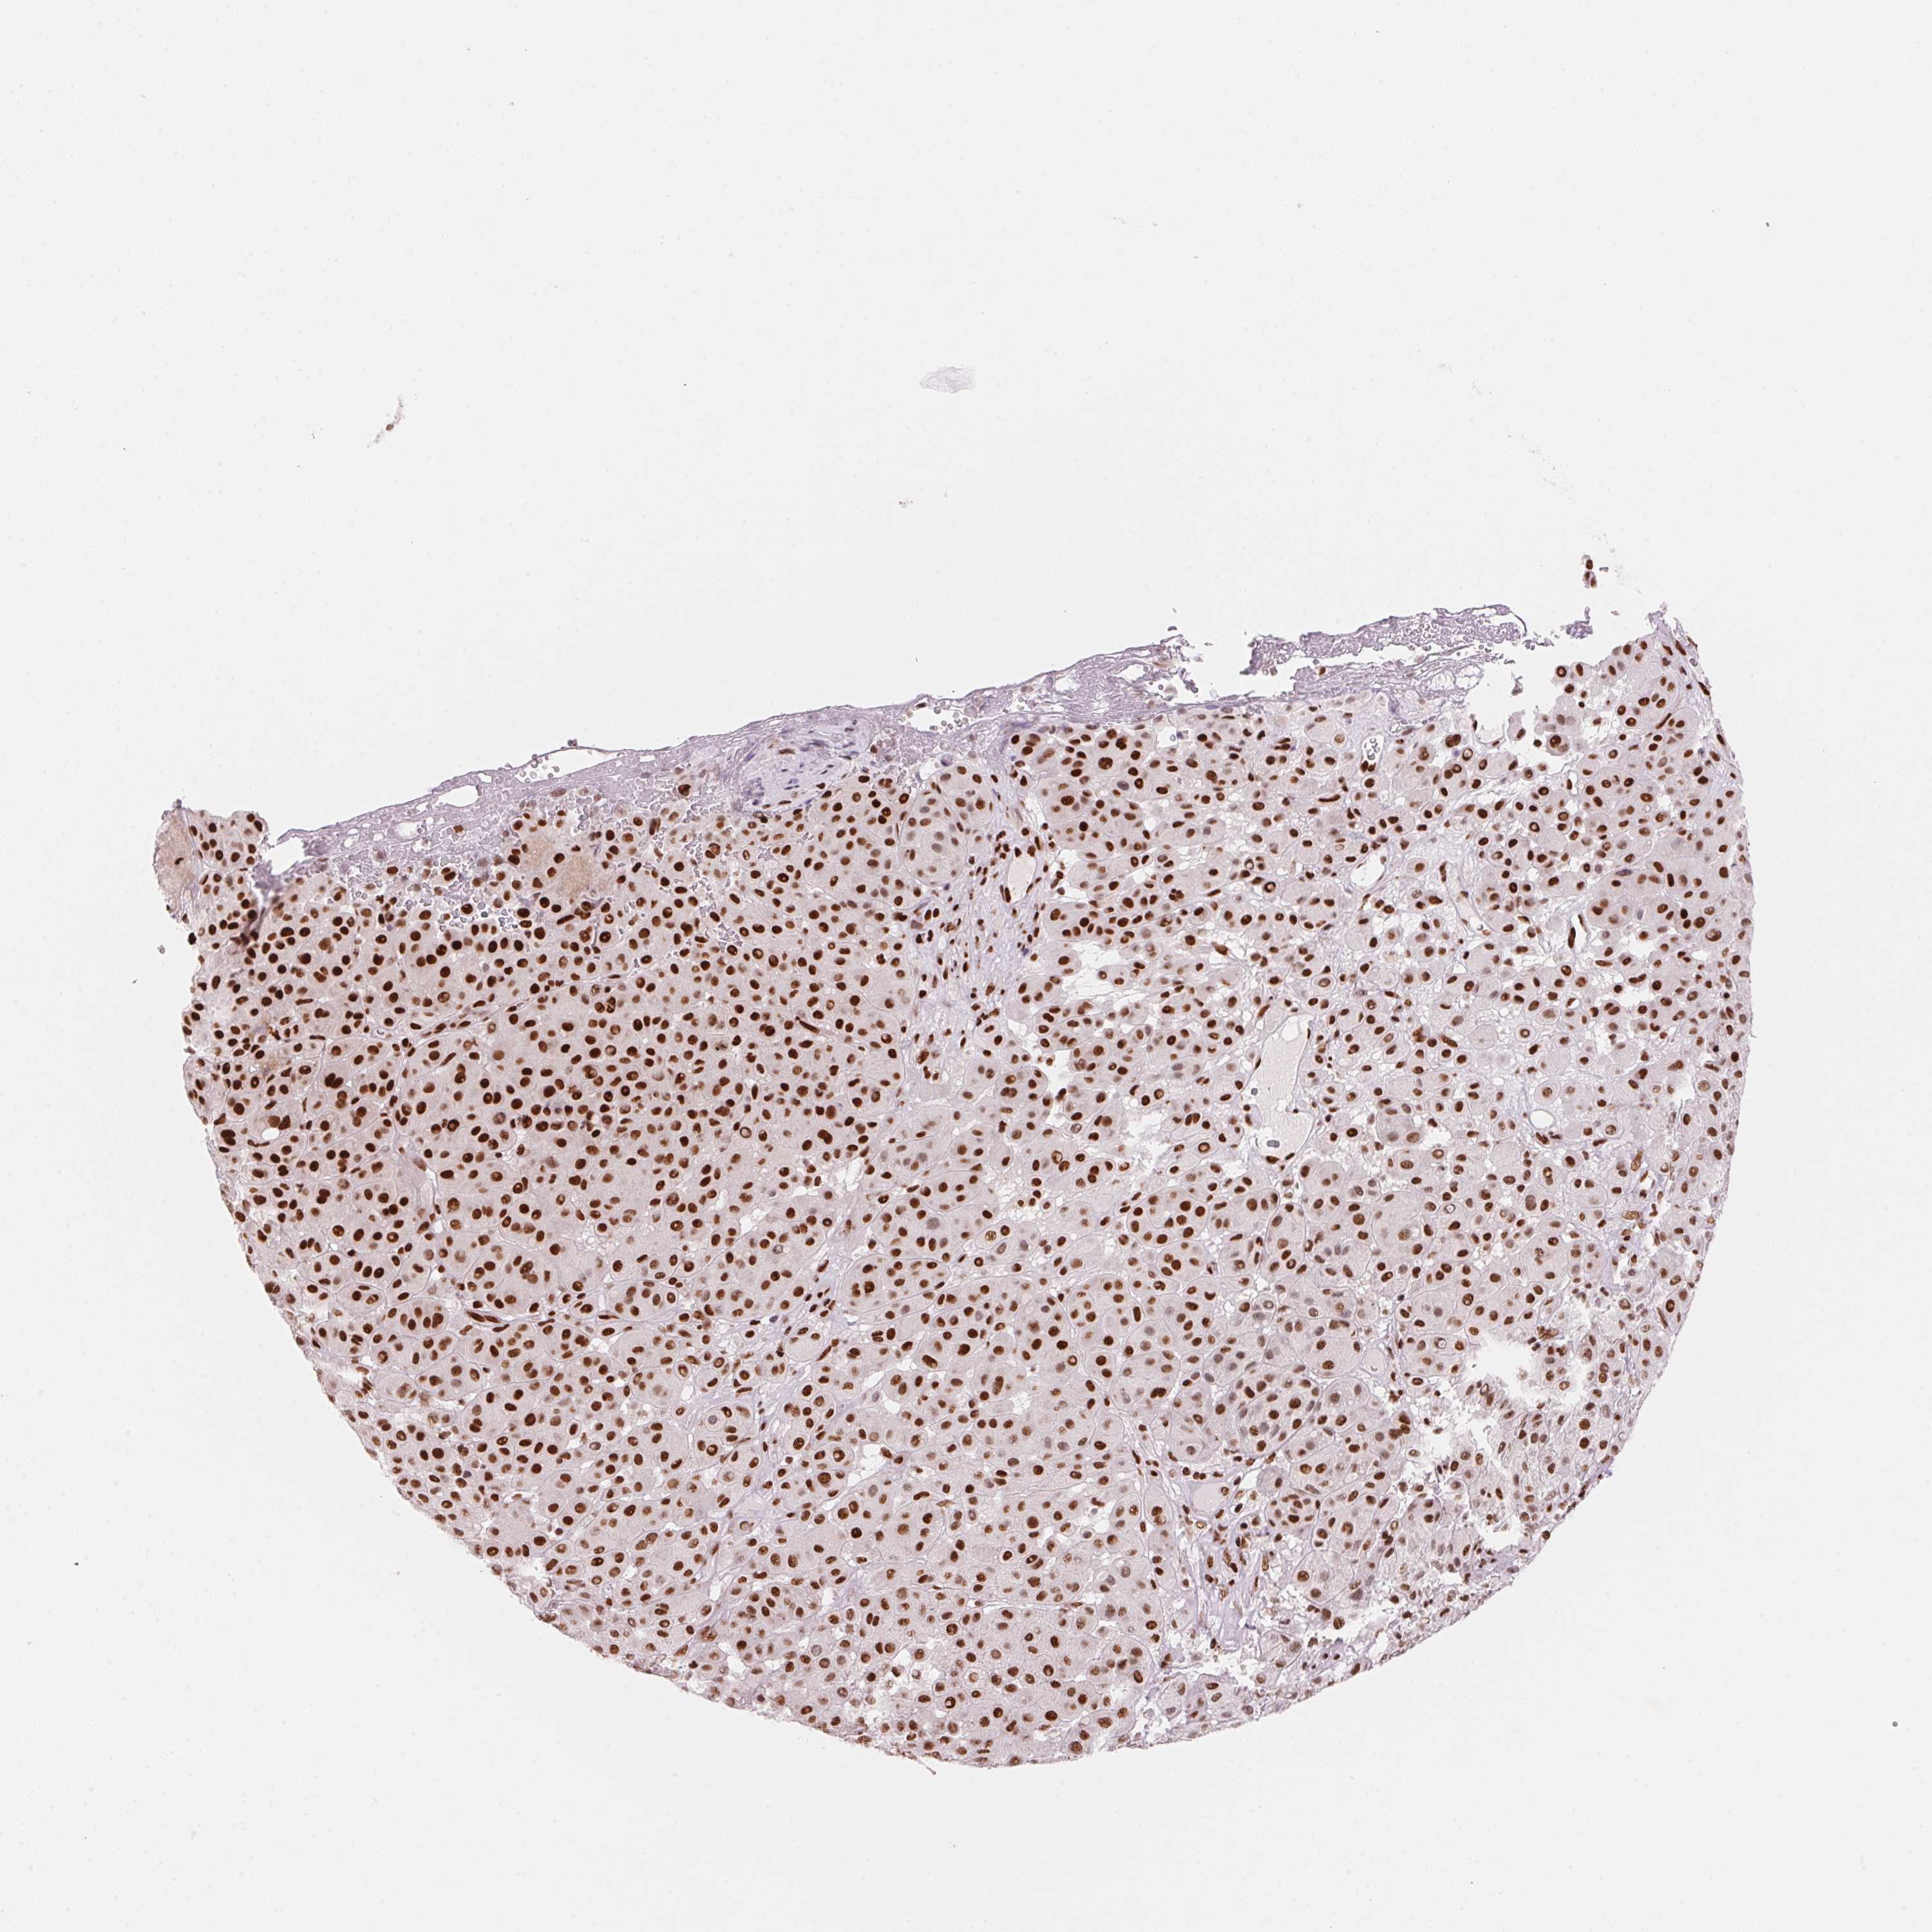

MELANOMA - Protein expressioni

A mouse-over function shows sample information and annotation data. Click on an image to view it in a full screen mode. Samples can be filtered based on level of antibody staining by selecting one or several of the following categories: high, medium, low and not detected. The assay and annotation is described here.

Note that samples used for immunohistochemistry by the Human Protein Atlas do not correspond to samples in the TCGA dataset.

Antibody stainingi

Antibody staining in the annotated cell types in the current human tissue is reported as not detected, low, medium, or high, based on conventional immunohistochemistry profiling in selected tissues. This score is based on the combination of the staining intensity and fraction of stained cells.

Each image is clickable and will lead to virtual microscopy that enables deeper exploration of all samples and also displays staining intensity scores, fraction scores and subcellular localization as well as patient and tissue information for each sample.

Antibody HPA061593

Antibody CAB016327

Staining

High

Medium

Low

Not detected

Intensity

Strong

Moderate

Weak

Negative

Quantity

>75%

75%-25%

<25%

None

Location

Nuclear

Cytoplasmic/membranous

Cytoplasmic/membranous,nuclear

Malignant melanoma, NOS

Malignant melanoma, Metastatic site